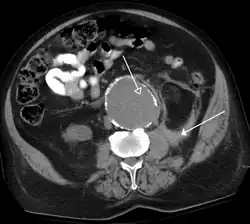

The most common technique is to perform portal venous phase imaging in the abdomen and pelvis (approximately 60–90 seconds after contrast administration, figure 2). This results in near optimal contrast opacification of the majority of the solid abdominal organs and it is used for a wide variety of indications: nonspecific abdominal pain; hernia; infection; masses (with a few exceptions such as hypervascular, renal, and some hepatic tumors); and in most follow-up examinations. As a general rule, this single phase is adequate unless there is a specific clinical indication that has been shown to benefit from other phases.

FIGURE 2. Contrast enhanced CT demonstrating parenchymal enhancement of the intra-abdominal organs in the portal venous phase (axial left, coronal reformat right).